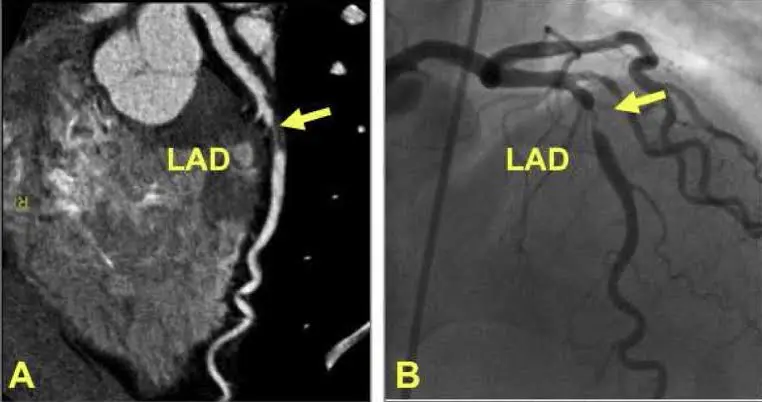

الأشعة المقطعية بالصبغة تتميز بدقتها العالية في تشخيص أمراض الشرايين التاجية. تسمح هذه التقنية برؤية الشرايين بوضوح تام وتحديد مواقع الانسدادات أو التضيقات. يعتبر هذا الفحص من الوسائل الفعالة لرصد اللويحات الدهنية والترسبات الكلسية.

مقارنةً بالفحوصات الأخرى مثل الأشعة السينية التقليدية، توفر الأشعة المقطعية صورًا ثلاثية الأبعاد. هذا يسهل على الأطباء تقييم حالة الشرايين بدقة أكبر. يمكن للأطباء بذلك تحديد خطورة الانسدادات والتخطيط للعلاج المناسب.

الأشعة المقطعية بالصبغة تتفوق على تقنيات تشخيصية أخرى في عدة جوانب. توفر هذه التقنية صورًا مفصلة ودقيقة للشرايين التاجية، مما يسمح بتشخيص أدق للمشكلات. على عكس الأشعة السينية التقليدية، تظهر الأشعة المقطعية الأوعية الدموية بتفاصيل ثلاثية الأبعاد.

في مقابل ذلك، تستخدم تقنية القسطرة القلبية لتوفير صور تفصيلية للشرايين. ومع ذلك، تعتبر القسطرة إجراء تدخلي أكثر، مما يزيد من المخاطر المرتبطة بها. الأشعة المقطعية، كونها أقل تدخلاً، تقلل من هذه المخاطر وتوفر بديلاً أكثر أمانًا للمرضى.